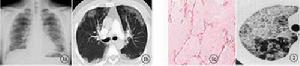

典型的胸片表現是雙肺對稱的肺泡填充性陰影,肺門旁的浸潤陰影延伸至外帶,呈“蝴蝶狀”分布,雙肋膈角往往不受累及。可是多數的PAP病例報導PAP的胸片沒有上述典型的特徵,因此X線胸片的表現通常不具有特異性。胸部HRCT能清晰地顯示肺部受累的範圍和特點。磨玻璃影與正常肺臟分界明顯,呈“地圖”樣分布;小葉內和小葉間隔增厚,呈多角形,稱為“鋪路石征”;或者表現為大片的實變影伴支氣管充氣征,周圍環繞著磨玻璃影。極少數病例有肺間質纖維化的表現,往往是疾病晚期。這些病變的程度和範圍與肺功能以及肺臟氣體交換障礙密切相關。

支氣管肺泡灌洗液具有特徵性的表現。外觀呈乳狀渾濁液體,靜置後沉澱分層。光鏡下可見非細胞性的圓形小體,姬姆薩染色呈嗜鹼性,PAS染色陽性;背景顯得“很髒”,可見大量的細胞碎屑,PAS染色陽性;巨噬細胞呈泡沫樣改變,胞漿內可見PAS陽性包涵體。淋巴細胞和漿細胞比例增高。電鏡下可見特徵性的髓樣多層狀結構和層狀小體,其成分是磷脂。